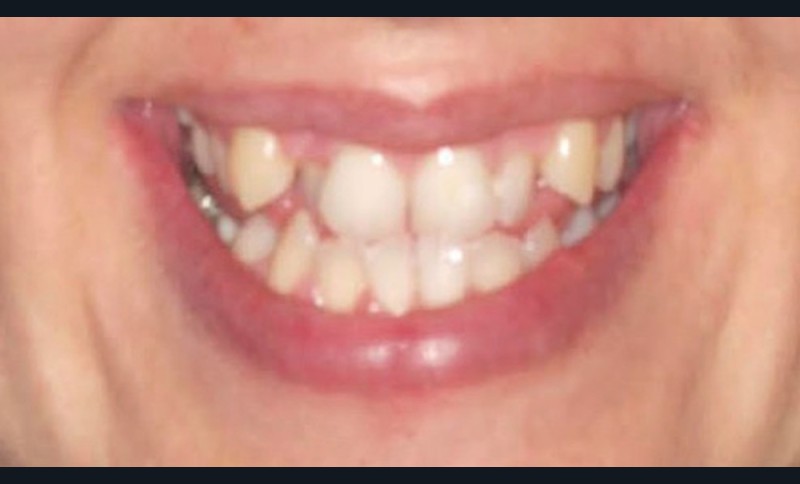

Le Pr Olivier Sorel insistera sur l’importance du respect des formes et des proportions anatomiques, pour éviter de voir apparaître, notamment chez les adultes, de très inesthétiques triangles noirs lors de la phase d’alignement (fig. 6a-b). Il présentera sa démarche diagnostique (évaluation de la forme des dents et de la dysharmonie dento-dentaire, fig. 7a-c) et l’intégration de la réduction amélaire proximale au plan de traitement, afin de s’assurer, en fin de traitement, la présence de papilles gingivales et donc d’un sourire harmonieux (fig. 8a-d).

Les Drs Marie Clément et Clara Marcoux aborderont ensuite les différents apports de la dentisterie esthétique aux traitements orthodontiques. Les problèmes de dyschromies isolées ou généralisées, congénitales ou acquises seront développés ainsi que les anomalies de proportions dentaires (dents riziformes…), le maquillage (transformation d’une canine en incisive latérale…) et le remplacement des dents antérieures. Les auteurs présenteront l’intérêt du Digital Smile Design dans le diagnostic et la communication et l’arsenal thérapeutique à notre disposition pour améliorer la satisfaction de nos patients (éclaircissement, traitement des taches de l’émail, composites stratifiés, fig. 9a-d).